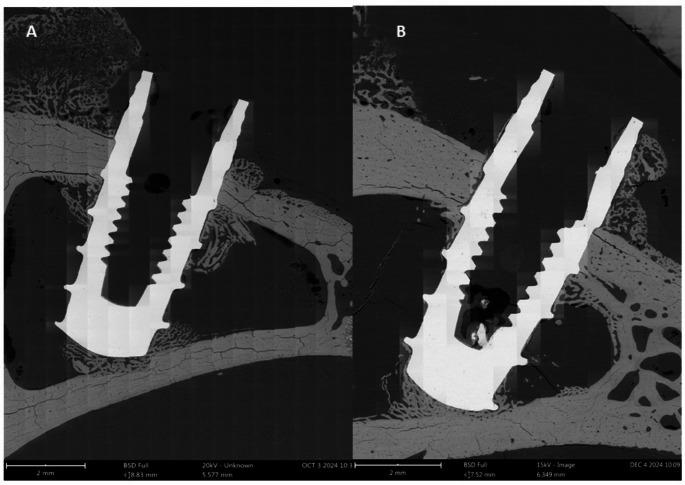

This layer has been obtained through a sulfuric acid treatment with hydrogen peroxide. It has been characterized using electron microscopy, the roughness was determined by confocal microscopy and wettability and surface energy assessed through contact angle. The incorporation of hydrogen was assessed using a fusion spectrometer. Fatigue behavior was evaluated with a servo-hydraulic testing machine. The adhesion of human osteoblastic cells SaOs-2 at 3 and 7 days was measured, and the level of mineralization was analyzed by alkaline phosphatase levels. Bacterial colonization assays were conducted using four strains to assess their bactericidal capacity. Implants were inserted into rabbit tibiae. After 21 days, the animals were sacrificed, and bone index contact determined.

A uniform surface created by nanospikes was obtained, exhibiting the same roughness as the control implant, no hydrogen was incorporated inside the titanium. The fatigue behavior showed no variation compared to the control. An increased wettability and higher surface energy compared to the control implant were noted. Enhanced osteoblastic adhesion was observed for the nanospikes surface in comparison with control at 3 days, with a significant level of alkaline phosphatase at 14 days, indicating a good degree of mineralization. The bactericidal capacity of nanospike surface is evidenced showing reductions ranging from 70 to 90%. In vivo tests demonstrate higher bone contact index values for dental implants with nanospikes (56%) compared to the control (41%).